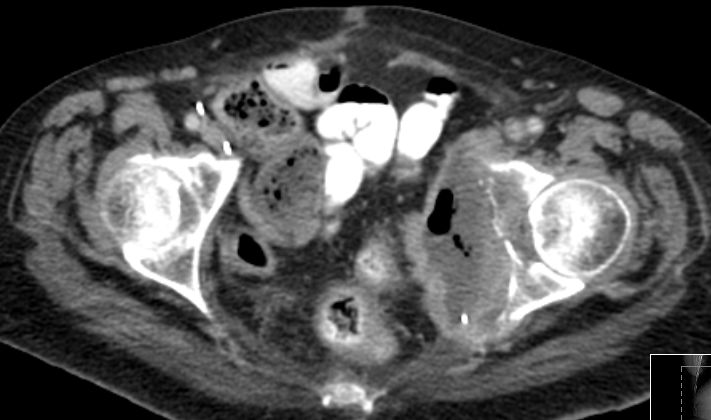

| Blase | 80-jähriger Mann mit ausgedehntem Blasentumor. Der Tumor

infiltriert auch das anliegende Fettgewebe und den Musculus rectus rechts .![]() |